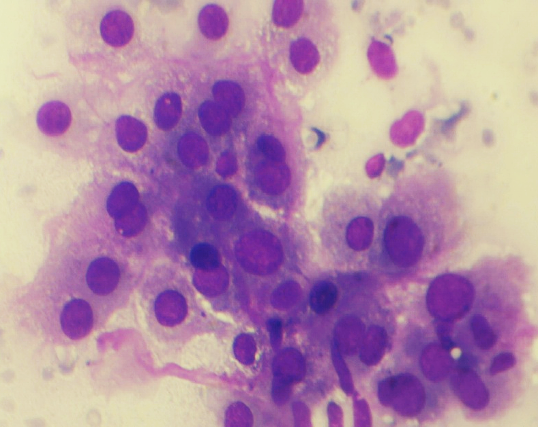

CYTOPATHOLOGY

Figs 1 and 2 from a mass in the right hypochondriac region.

Make your diagnosis.

Fig 2 : Giemsa x 400